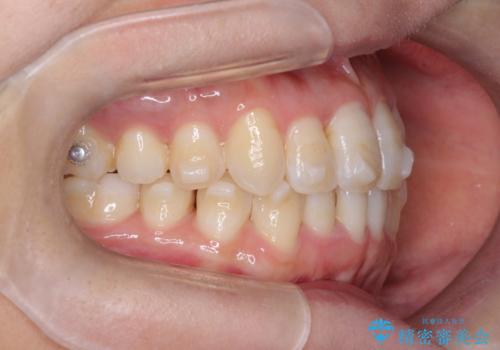

【インビザライン】前歯の凸凹をなおしたい

- 前歯の凸凹を主訴に来院されました。

上顎の急速拡大を行なったのちインビザラインにて治療を行なっております。

今回のケースは後戻りのリスクを低くし、またディスキング量を減らすために上顎の急速拡大を行なっております。